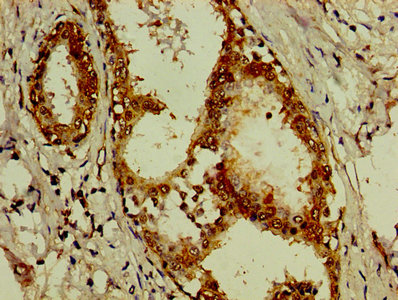

IHC image of CSB-PA00814A0Rb diluted at 1:200 and staining in paraffin-embedded human breast cancer performed on a Leica BondTM system. After dewaxing and hydration, antigen retrieval was mediated by high pressure in a citrate buffer (pH 6.0). Section was blocked with 10% normal goat serum 30min at RT. Then primary antibody (1% BSA) was incubated at 4°C overnight. The primary is detected by a biotinylated secondary antibody and visualized using an HRP conjugated SP system.